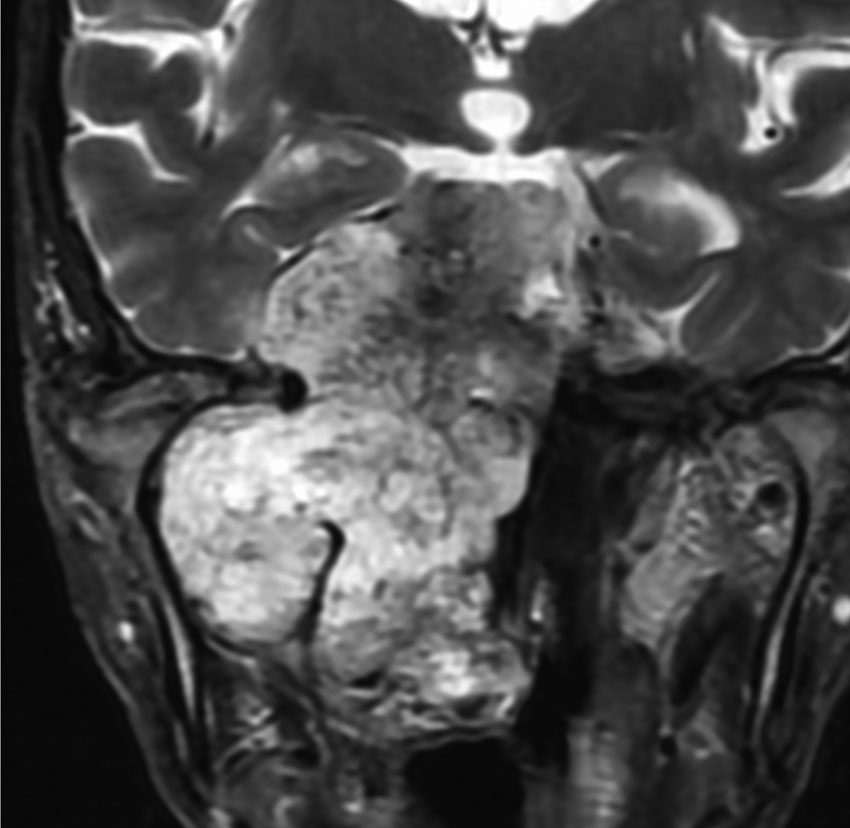

斜台の脊索腫 classical type

CTでは,斜台から左蝶形骨にかけて不規則な骨破壊像がみられます。

MRI T2強調画像(左)では等信号から高信号のまだらな境界が不明瞭な腫瘍が斜台から左海綿静脈洞内に浸潤しているのがみられます。T1強調ガドリニウム増強では,腫瘍がまだらに増強されています。トルコ鞍から鞍上部に伸び,視交差を侵し第3脳室底まで伸展しています。脊索腫が硬膜内に浸潤して神経組織と癒着することは珍しいことではありません。